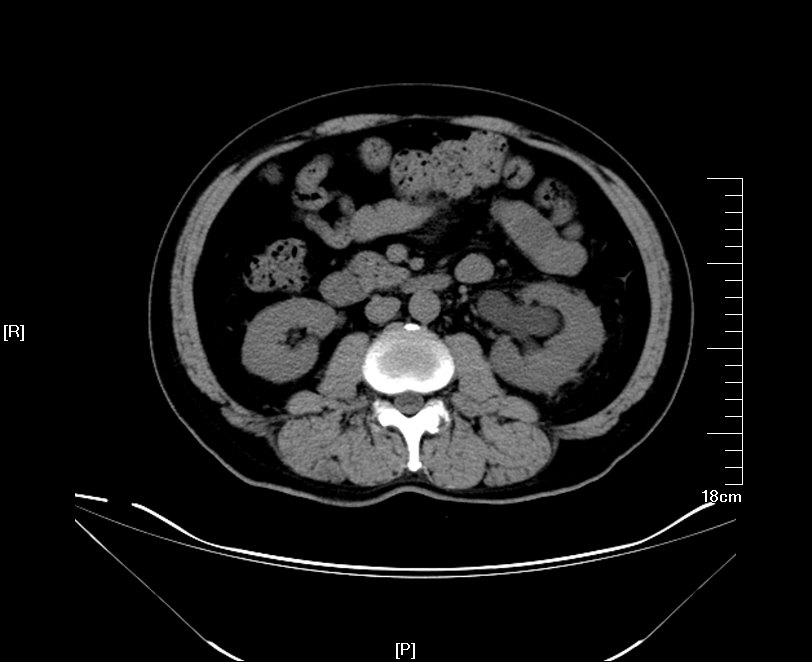

右侧双肾盂畸形!

这是一个左肾的重复肾畸形合并左上肾积水.